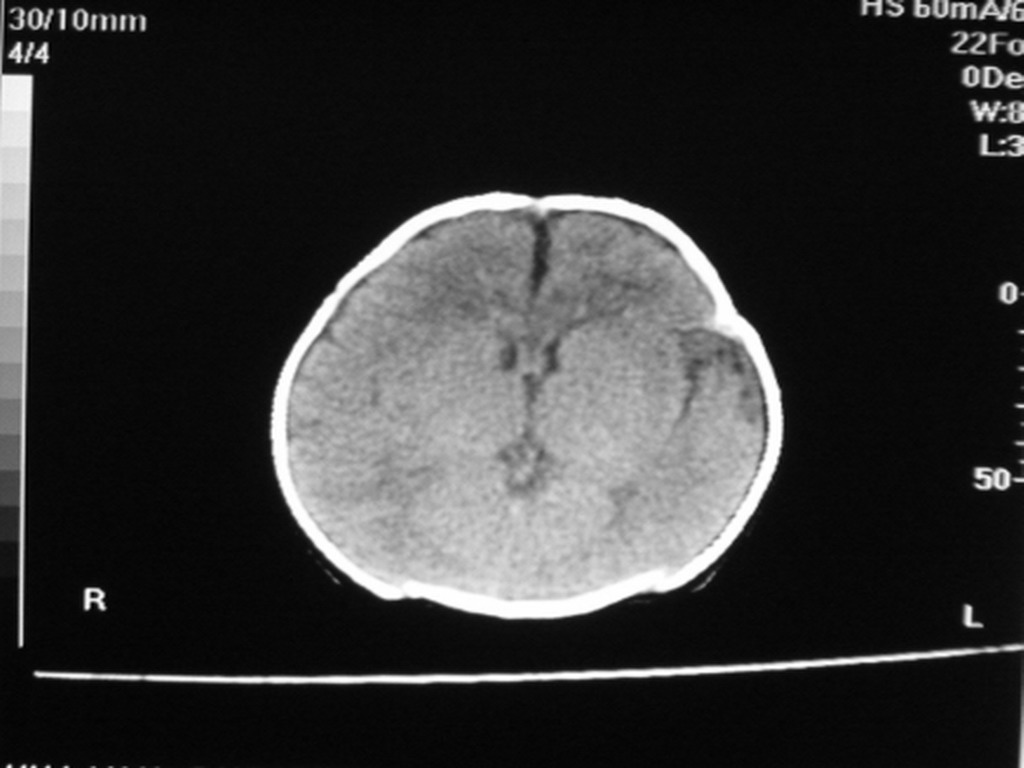

标题: PED1877:女,20余天,突发抽搐,双眼凝视。 [打印本页]

女,20余天,突发抽搐,双眼凝视。